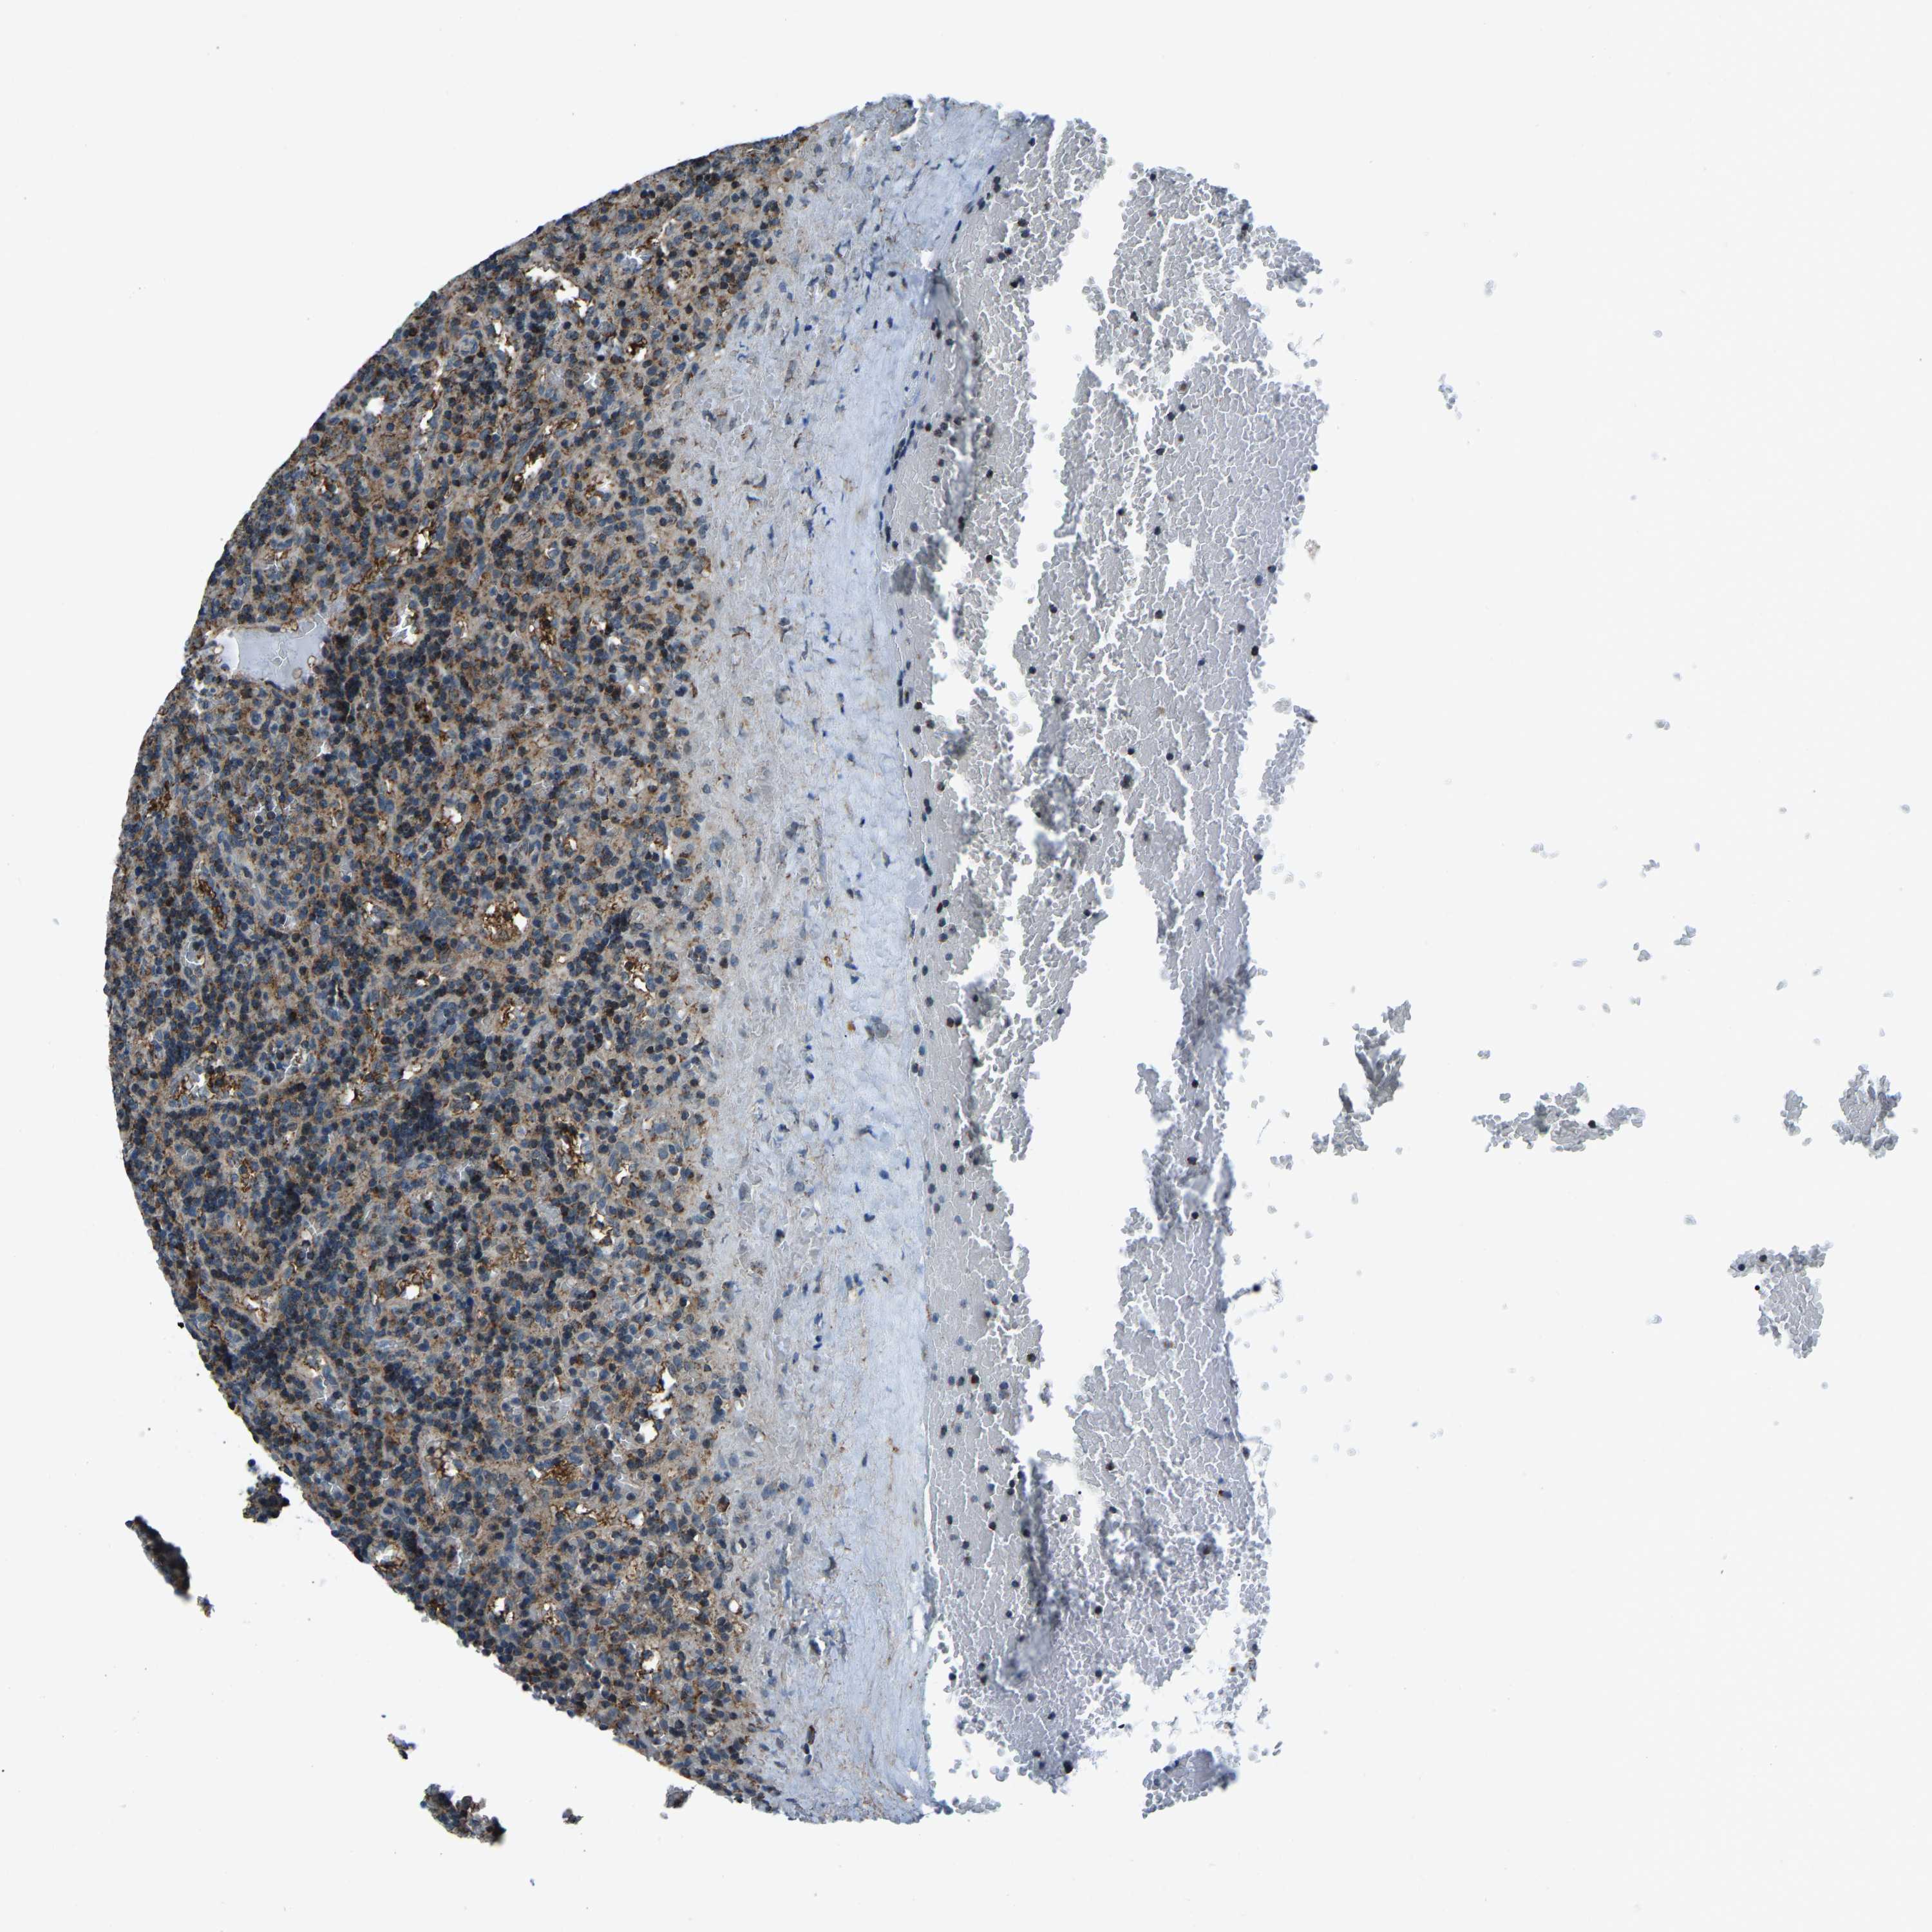

CANCER LYMPHOMA Show tissue menu

LYMPHOMA - Protein expressioni

A mouse-over function shows sample information and annotation data. Click on an image to view it in a full screen mode. Samples can be filtered based on level of antibody staining by selecting one or several of the following categories: high, medium, low and not detected. The assay and annotation is described here.

Each image is clickable and will lead to virtual microscopy that enables deeper exploration of all samples and also displays staining intensity scores, fraction scores and subcellular localization as well as patient and tissue information for each sample.

Antibody HPA019232

Antibody HPA021497

Antibody HPA021768

Hodgkin's disease, NOS

Malignant lymphoma, non-Hodgkin's type, High grade

Malignant lymphoma, non-Hodgkin's type, Low grade